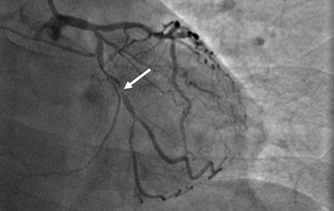

近日,河北醫(yī)科大學(xué)附屬燕達(dá)醫(yī)院心血管內(nèi)三科成功完成一例非常特殊的手術(shù)——冠心病三支病變微創(chuàng)介入完全血運(yùn)重建術(shù)。患者李先生冠心病病變極其嚴(yán)重,全部三支主干動(dòng)脈均重度狹窄,各處求診均被告知無(wú)法微創(chuàng)介入手術(shù),只能開(kāi)胸搭橋。拒絕開(kāi)胸的李先生慕燕達(dá)醫(yī)院心血管內(nèi)三科北京安貞醫(yī)院專家團(tuán)隊(duì)之名,就診于燕達(dá)醫(yī)院,由翟光耀主任為其行 “一站式”手術(shù),一 次 性完成三支動(dòng)脈的修復(fù)!手術(shù)非常成功,李先生術(shù)后恢復(fù)良好,滿意出院。   震驚 患者三支血管均90-99%狹窄 ..